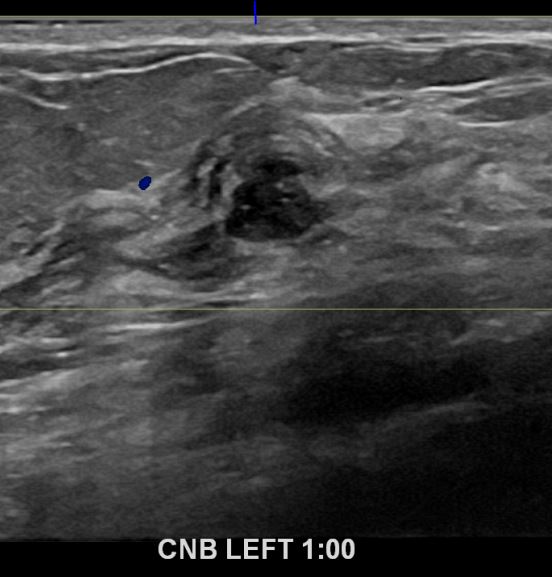

상기환자 외부검사상 이상소견으로 내원하신 50대 후반 여성분으로

좌측 조직검사 시행해 침윤성 유방암으로 진단되었습니다.